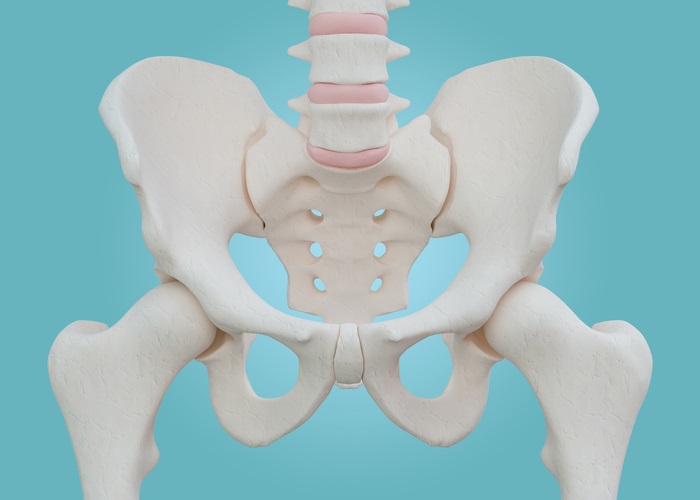

고관절은 엉덩이관절이라고도 불리우며, 보통 알고있는 골반위치에 있고, 공처럼 둥글게 생긴 대퇴골두가 글러브가 감싼듯한 모양으로 비구에 맞물려 있어요.

이렇듯 고관절은 오목하게 들어간 비구와 둥근 공모양의 대퇴골두로 이루어져 있으며 골반과 다리를 이어주는 우리 몸의 핵심 관절인데요. 그리고 고관절은 골반을 통해 전달되는 체중을 지탱해주고 걷기와 달리기같은 다리 운동들을 가능하게 해주는 관절이기도 해요.